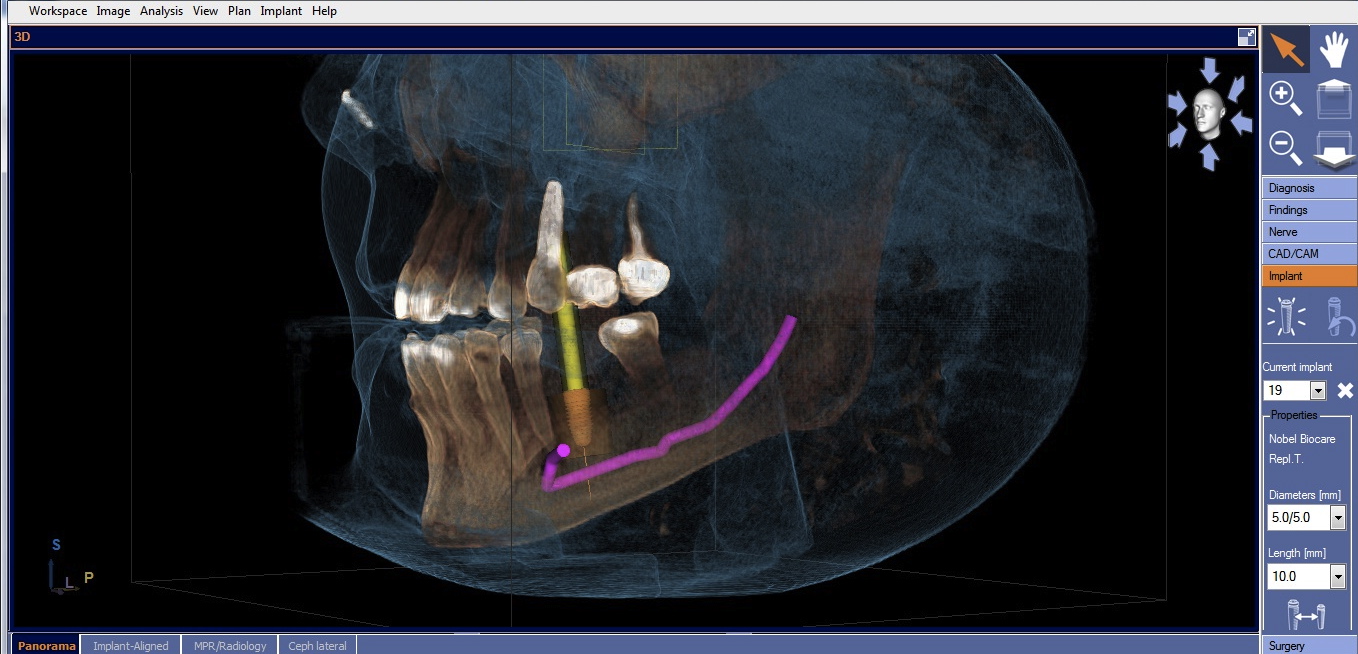

Once the desired restorative outcome is in a digital format, the patient’s CBCT scan is opened in the implant-planning software. If the edentulous space is in the posterior mandible, the inferior alveolar nerve bundle (IANB) is traced so that it is highlighted and avoided by the planned implant (Figure 2). Now, the patient’s digital restoration can be imported. Once imported, most software requires the user to identify corresponding landmarks on the digitized model and on the CBCT to merge the two data sets. It is best to avoid using teeth with crowns or large restorations as landmarks, because they cause distortions in CBCT scans and may result in inaccuracies in data set merges. Once complete, merge accuracy is verified by the user and is either confirmed or reset.

Cone-beam computed tomography (CBCT) with traced and highlighted inferior alveolar nerve bundle (IANB).

Figure 2

CBCT with final implant plan. Note the digital restoration, TiBase abutment, and highlighted IANB.

Figure 3